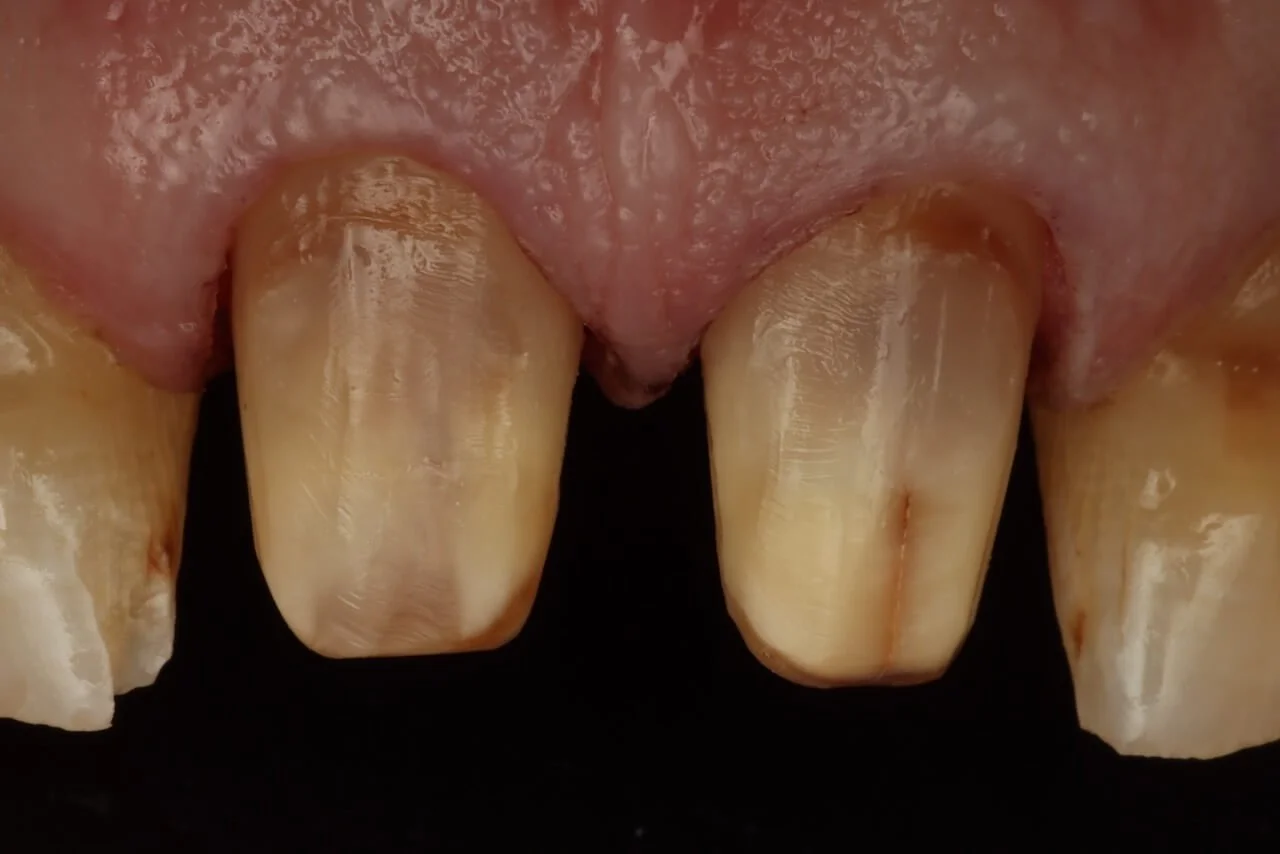

Once you go Verti, Shoulders feel Dirty! Learn why vertical preparation margins are revolutionizing adhesive dentistry—and how to execute them flawlessly every time.

Vertical preparation margins offer significant advantages over traditional shoulder preparations—but only when executed correctly. This course removes the guesswork and gives you the complete system for integrating vertipreps into your practice with predictable, beautiful results.